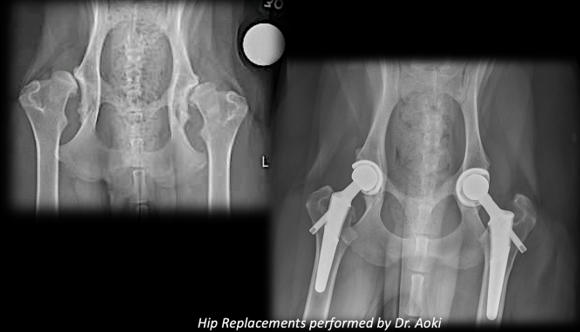

TOTAL HIP REPLACEMENT (THR) FOR DOGS

We are pleased to offer Total Hip Replacement (THR) for canine patients suffering from severe hip disease.

Total hip replacement is considered the gold standard surgical treatment for advanced hip conditions when medical management is no longer effective.

Total hip replacement involves removing the diseased hip joint and replacing it with a prosthetic joint designed to restore normal function. At WAVES, we utilize both cemented and non-cemented implant systems, allowing us to tailor treatment to your dog’s age, size, bone quality, and individual anatomy. Our goal is long-term pain relief and a return to comfortable, active living.